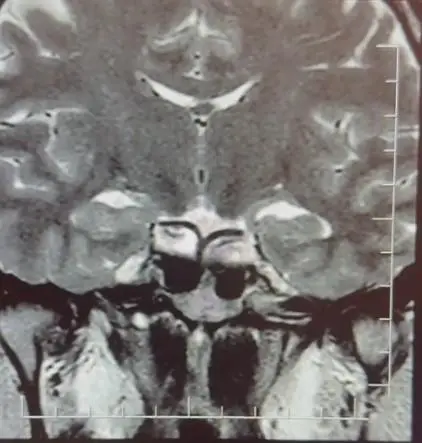

İlk olarak yapılan idrar testinde hamilelik hormonu (hCG) seviyeleri normal çıktı. Ardından yapılan ultrason ve kan testleri, kadının polikistik over sendromu (PKOS) ve tiroid fonksiyon bozukluğu belirtileri gösterdiğini ortaya koydu. Bu durum, hamilelik belirtilerine benzer semptomların ortaya çıkmasına neden oluyordu.